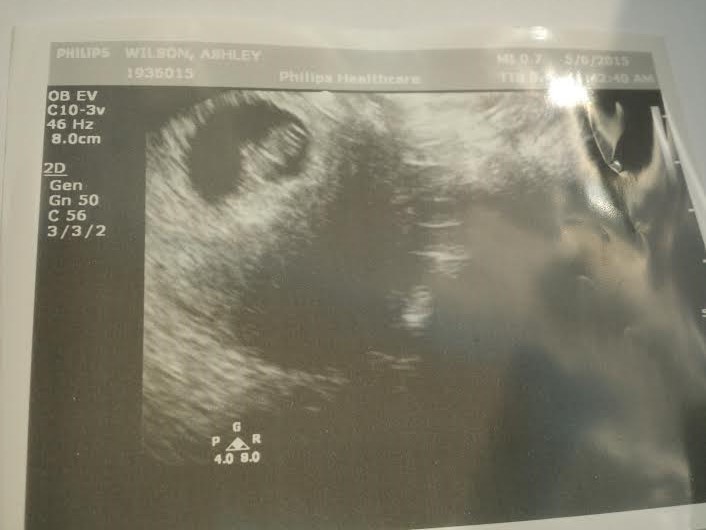

So I started the plan and the first couple of days were a little rough because your body has to adjust to new and better habits. Within the time frame of me being on the plan, I lost 14 pounds AND I FELT SO MUCH BETTER!!!!! My hormones were finally regulated and I just truly felt good. I thank God often from healing me from those symptoms and sending BeBalnced as a resource to help me in that as well. I would say after a month or two of finishing the plan…we found out about our little bun in the oven. The joy of feeling better must of flowed to other areas as well! haha!